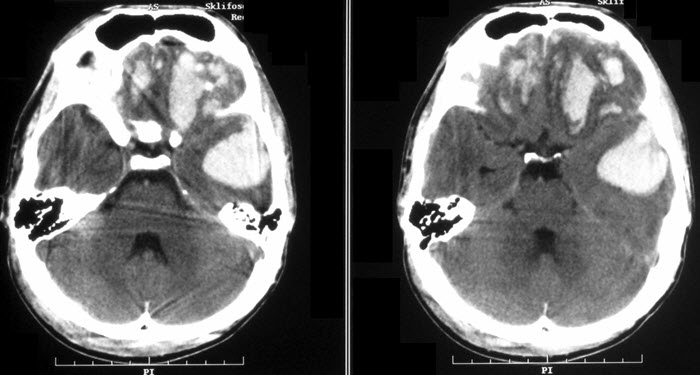

- Информативна при поражении магнитно-резонансная томография. Она позволяет визуализировать структуры головного мозга, выявить аномалии строения черепа, церебральных и сосудистых соединений. Применяется этот метод и для подтверждения наличия опухолевых процессов.